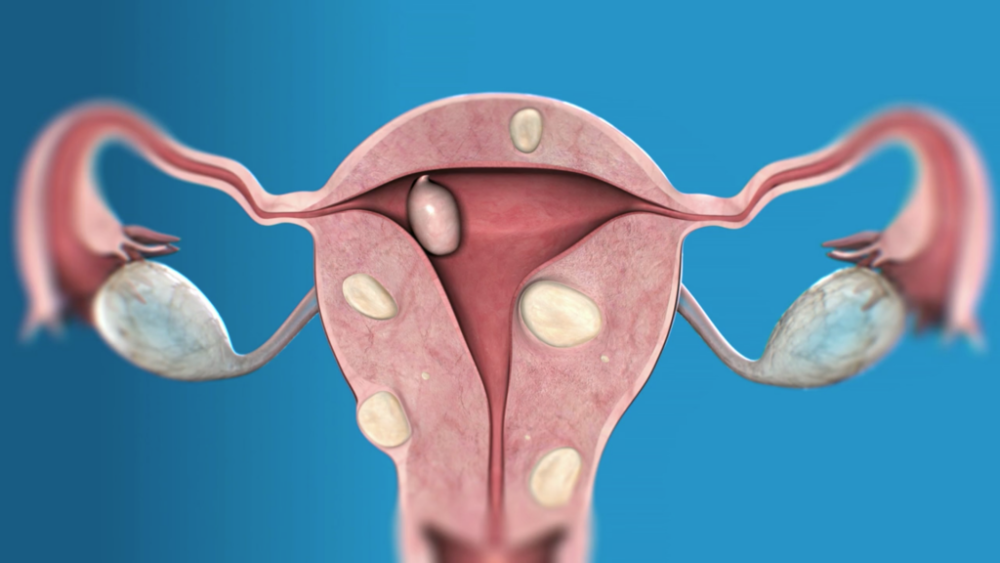

Les fibromes (aussi appelés léiomyomes ou myomes) sont des tumeurs bénignes formées en partie de tissus musculaires. Ils se développent rarement dans le col de.

Myome: causes et facteurs de risque. Comment exactement il vient à un fibrome dans l'utérus est encore inconnu. Les scientifiques soupçonnent que l'hormone féminine.

Qu’est ce qu’un fibrome ou myome ? Un « fibrome » de l'uterus encore appelé par les médecins Myome, est une tumeur bénigne faite de la prolifération de cellules.

Qu'est-ce qu'un myome ? Le myome, ou fibrome, utérin est une tumeur bénigne de l'utérus qui se développe au sein du muscle lisse. Il n'y a pas de risque que cette.

QUEST PROVOQUE MYOMES FEMME : La cause exacte des fibromes est inconnue, mais les hormones et les facteurs de croissance semblent jouer un rôle. La croissance des.